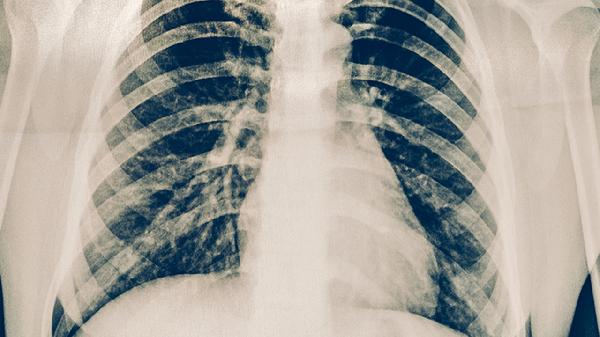

苏州入职体检价格一般在100-300元,具体费用与体检项目、机构类型等因素相关。公立医院基础套餐通常在150-200元,民营体检机构常有100-150元的促销套餐。苏州入职体检费用差异主要体现在项目组合和服务形式上。基础套餐包含内科、外科、血常规、尿常规、肝功能、胸透等项目,价格区间为100-150元。若增加心电图、B超等项目,费用可能达到200-300元。...